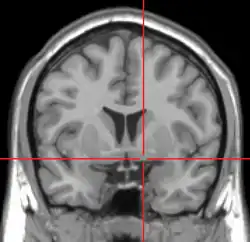

MRI showing a coronal plane of the head with marks showing the location of the substantia innominata, the region in which the nucleus basalis is found. | |

The nucleus basalis in humans is a somewhat diffuse collection of large cholinergic neurons in the basal forebrain.[2] The main body of the nucleus basalis lies inferior to the anterior commissure and the globus pallidus, and lateral to the anterior hypothalamus in an area known as the substantia innominata.[1] Rostrally, the nucleus basalis is continuous with the cholinergic neurons of the nucleus of the diagonal band of Broca.[1] The nucleus basalis is thought to consist of several subdivisions based on the location of the cells and their projections to other brain regions.[2] Occasional neurons belonging to the nucleus basalis can be found in nearby locations such as the internal laminae of the globus pallidus and the genu of the internal capsule.[1]